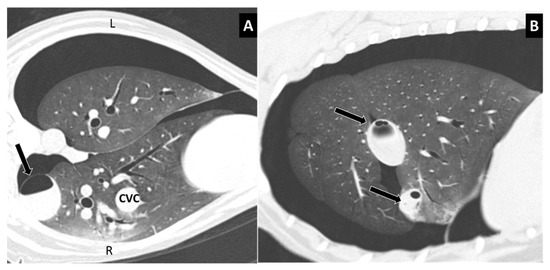

Figure 5.

(A) Type 3 lung laceration (arrow) associated to rib fracture. Note the increased opacity in the lung parenchyma surrounding the laceration, consistent with pulmonary hemorrhage, and the pneumothorax. (B) Type 4 small subpleural lung lacerations not associated with rib fracture.